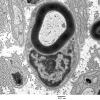

PERIPHERAL NEUROPATHY

2 NORMAL AXON (2)